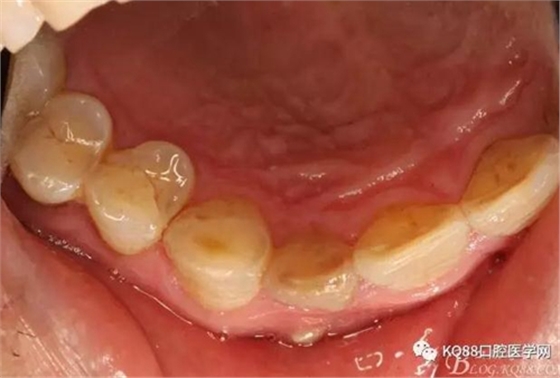

一個月后患者復查: 唇側觀:11根尖區(qū)粘膜有一膿瘺,捫診溢膿,牙冠成灰褐色。根管治療無法治愈根尖病變,建議根管外科治療,患者同意手術。

圖3.腭側觀;11腭側牙齦正常,21腭側樹脂充填完好